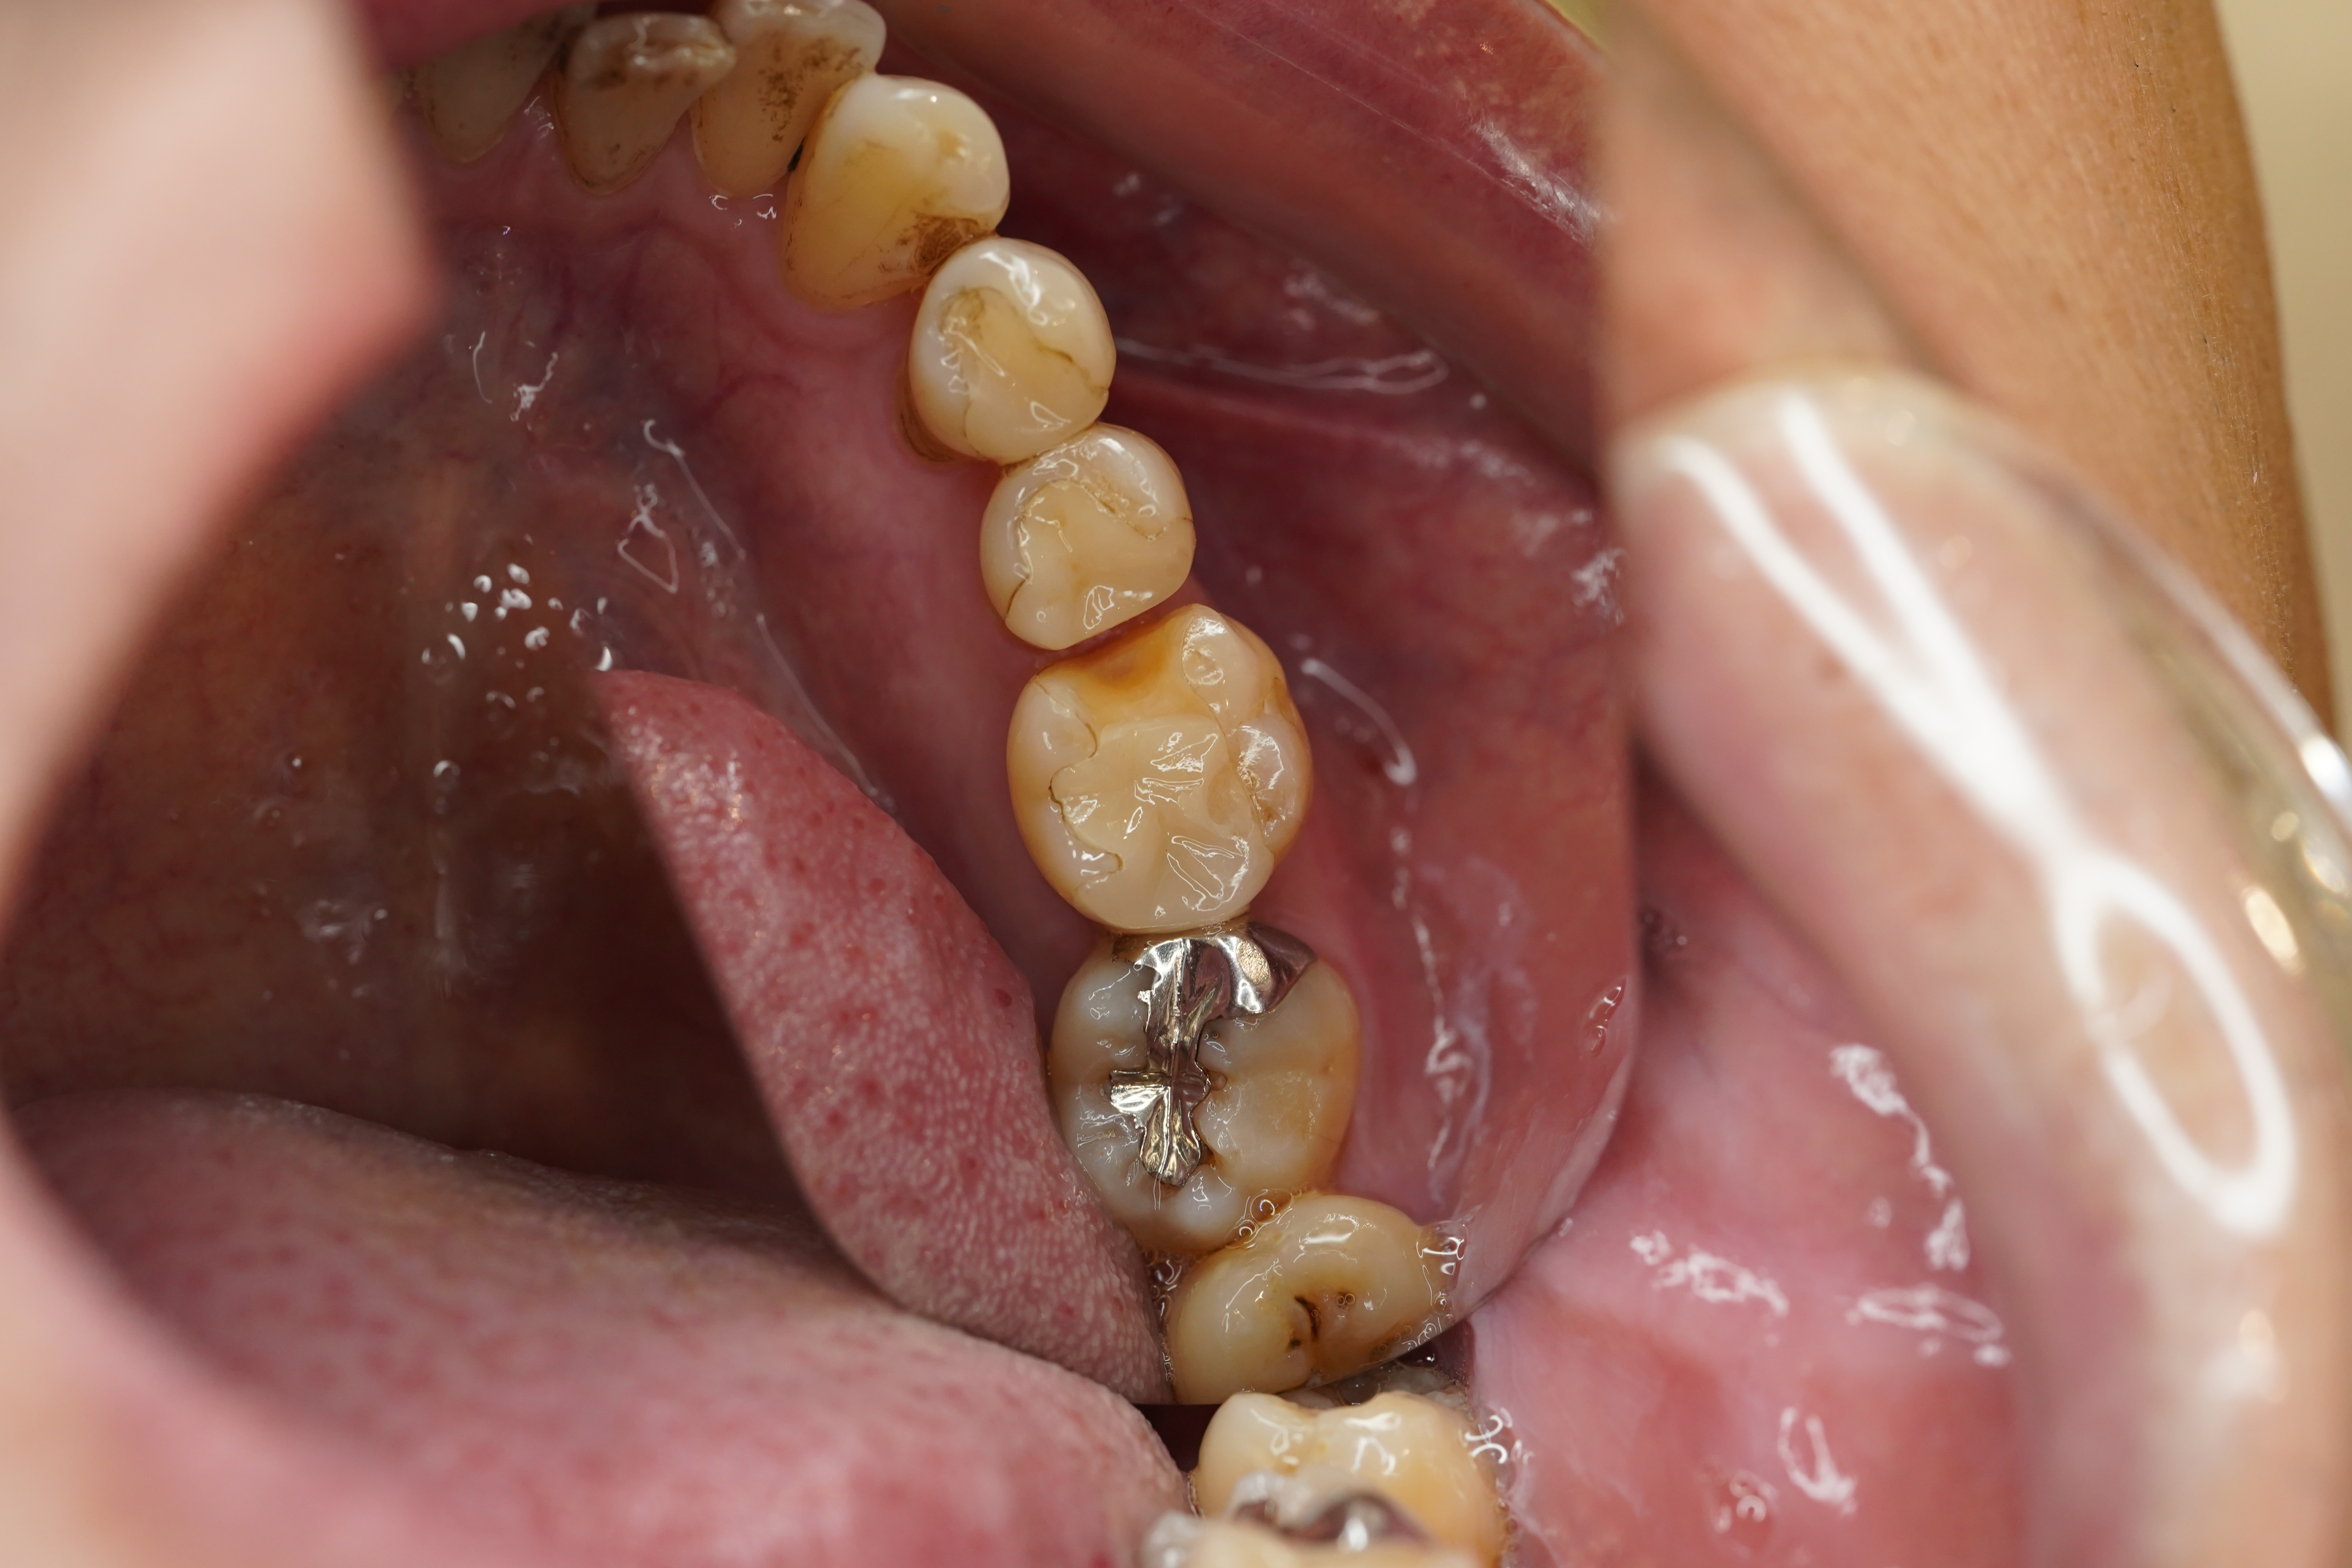

今回は逗子の患者さまで他院で治療した左下第一大臼歯のセラミックの詰め物が破損してしまいMTAセメントとフルジルコニアで治療したケースのご紹介です💡

こちらが処置前のPhotoになります

もともとセラミックで作られたインレーといわれる詰め物が入っていました

その詰め物の一部が割れて取れてしまい来院されました

治療をし直すには今入っている詰め物を全て除去しなくてはなりません

そうすると天然歯の残る部分が少なくなるので今回はクラウンといわれる被せ物で修復することとなりました

また神経が生きている歯でしたので先にMTAを行いました